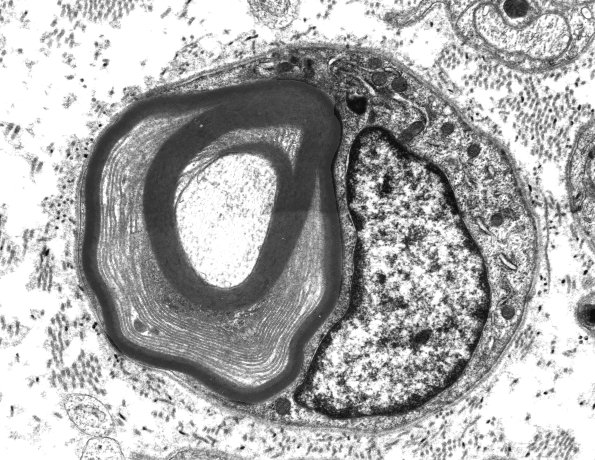

An additional lesion with prominent UCM. (electron micrograph)